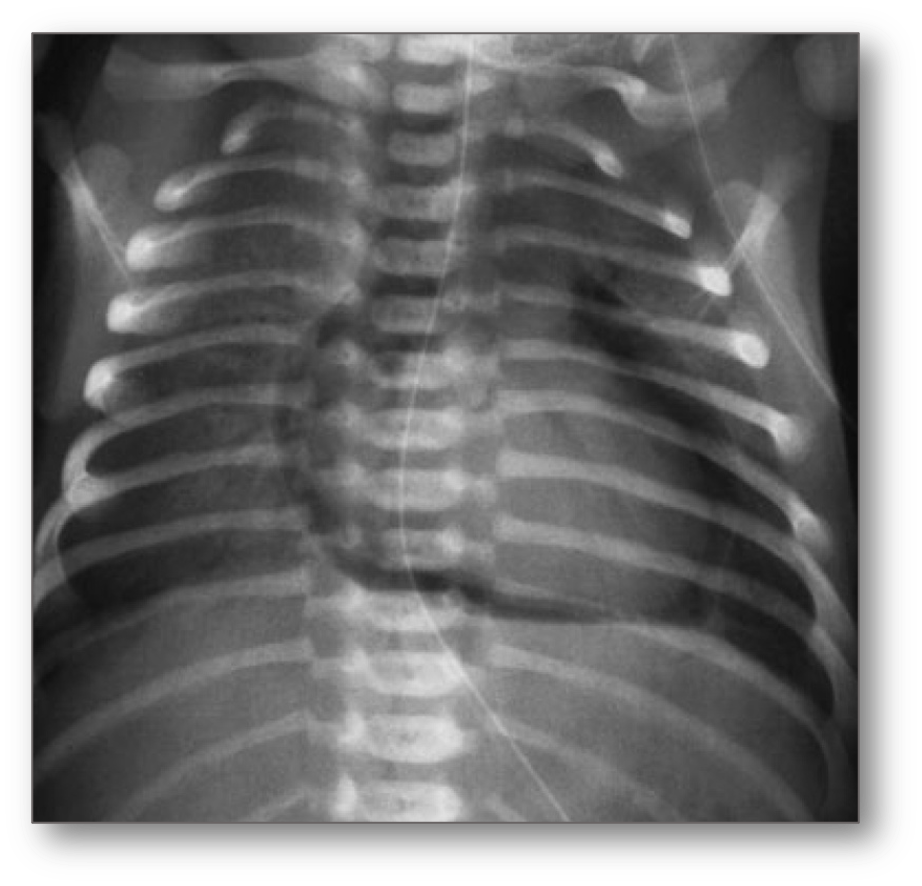

Transpulmonary pressures that exceed the strength of the terminal airways and alveoli can damage the respiratory epithelium. The air enters the interstitium, causing pulmonary interstitial emphysema, then dissection of air toward the visceral pleura and/or the hilum through the peribronchial and perivascular spaces.